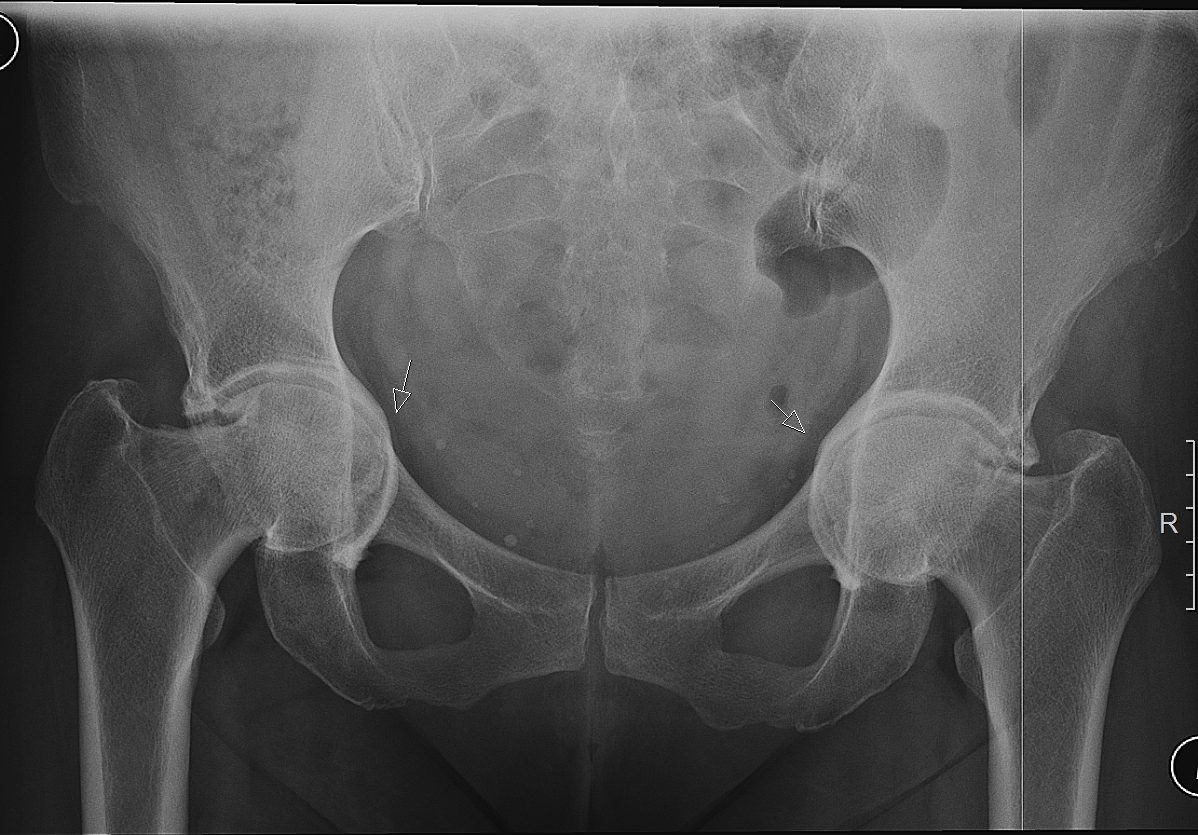

Клинический наблюдения и методы. Под нашим наблюдением с 2008г. по настоящее время находилось 172 пациента с коксартрозом 1-2 стадии в возрасте от 26 до 72 лет, с давностью заболевания от 1 до 20 лет. Мужчин было 51 (30%), женщин 121 (70%).

У 674 пациентов (43 %) отмечено сочетание коксартроза с остеохондрозом. Двухстороннее поражение тазобедренных суставов наблюдалось в 29% случаев.

На рентгенограммах тазобедренный сустав сохраняет нормальную форму, суставная щель умеренно или неравномерно сужена с субхондральным склерозированием костных суставных поверхностей, непостоянными краевыми костными разрастаниями (I стадия).

У 116 (67.5%) пациентов имелись постоянные боли, иррадиирующие в бедро, паховую область, хромота, значительное ограничение движений, ограничение внутренней ротации и отведения, непостоянный хруст в суставе при движении.

Рентгенологически суставная щель может быть равномерно или неравномерно сужена, ацетабулярная суставная впадина уплощена, присутствуют явления субхондрального склероза, краевые костные разрастания. Конфигурация головки бедренной кости, как правило, не нарушена (II стадия).

В подавляющем большинстве случаев диагноз коксартроза ставится при рентгенографии, где видны изменения формы и структуры костей, составляющих тазобедренный сустав. Однако рентгенографически в ряде случаев затруднительно зафиксировать ранние проявления артроза, так как хрящевая ткань суставных поверхностей на рентгеновских снимках не отображается и мы можем судить о дегенеративном процессе, когда он достаточно выражен, вызывая изменения ширины просвета рентгеновской суставной щели.